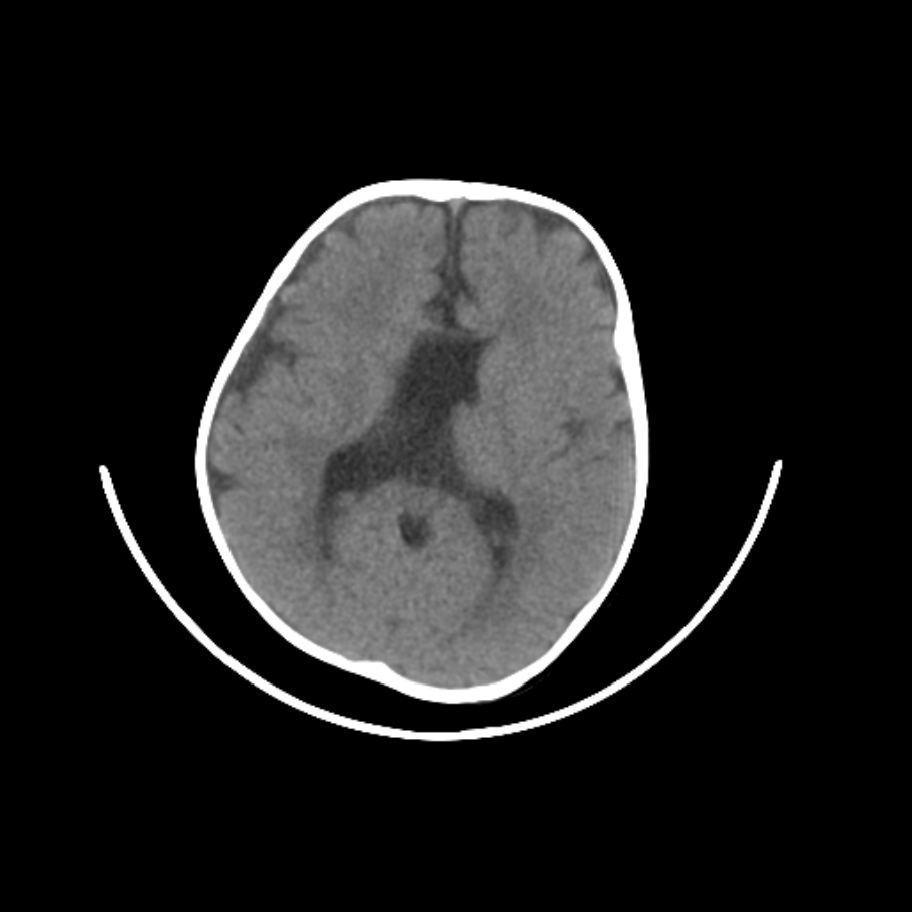

以下是引用随光逐影在2009-4-8 7:51:00的发言:[br]1)透明隔缺如(视-隔发育不良?)。2)右侧脑裂畸形。3)右侧幕上半球脑萎缩。